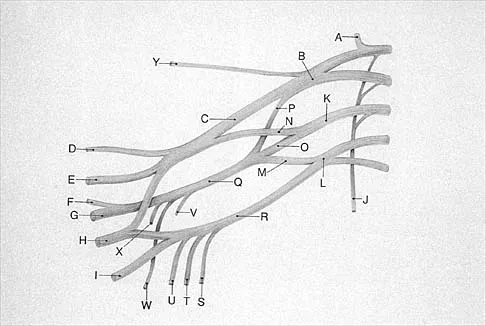

What structure is marked Q in the diagram of the brachial plexus shown in Figure 22?